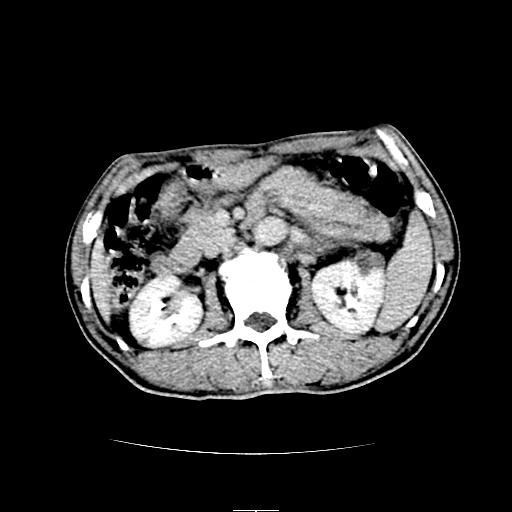

左上腹胃、脾及胰腺间巨大囊性占位性病变,内见多数薄隔,有轻度强化,明显占位效应。左肾见一小囊肿。

考虑:1、左上腹巨大囊肿(可能来源于胰腺)。

2、左肾小囊肿。

左上腹胃、脾及胰腺间巨大囊性占位性病变,内见多数薄隔,有轻度强化,明显占位效应,胰腺及左肾结构清楚,明显向后下方推压 移位。左肾见一小囊肿.多考虑:1 网膜巨大囊肿。2 左肾小囊肿。

1胃脾胰之间一巨大囊性影,胃明显向前推移,胰体尾部似肥大,考虑囊性影来源于胰腺(假性囊肿?)2左肾小囊肿。

左上腹囊性占位,与胰腺分界不清,考虑起源于胰腺可能。

左上腹囊性占位,虽与胰腺分界不清,胰尾似乎受压前移,病灶最大截面并不在胰腺水平,考虑来源于网膜可能性大吧,应再详细追问病史.

左上腹胃、脾及胰腺间巨大囊性占位性病变,其内见多数薄隔,有轻度强化,明显占位效应。左肾见一小囊性变。

左肾囊肿;网膜巨大囊肿。